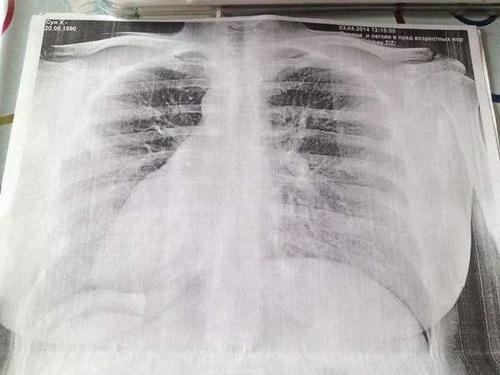

女生的胸透步骤,女生的胸透胸片

问:我想知道这个胸透的阴影可能是什么

女生的胸透胸片

女性胸透图片

胸透图片

胸透正常图片

肺癌胸透图片